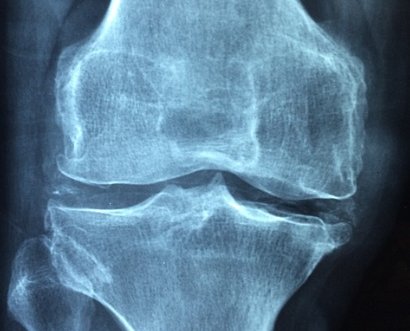

3. 골다공증과 뼈 통증

비타민d는 칼슘과 인의 흡수를 돕는 역할을 합니다. 부족하면 골밀도가 감소하고 뼈가 약해져 골다공증으로 진행될 위험이 커집니다.

뼈가 약해지면 허리, 무릎, 손목 등에서 통증을 느끼기 쉽고, 작은 충격에도 골절될 가능성이 높아집니다.